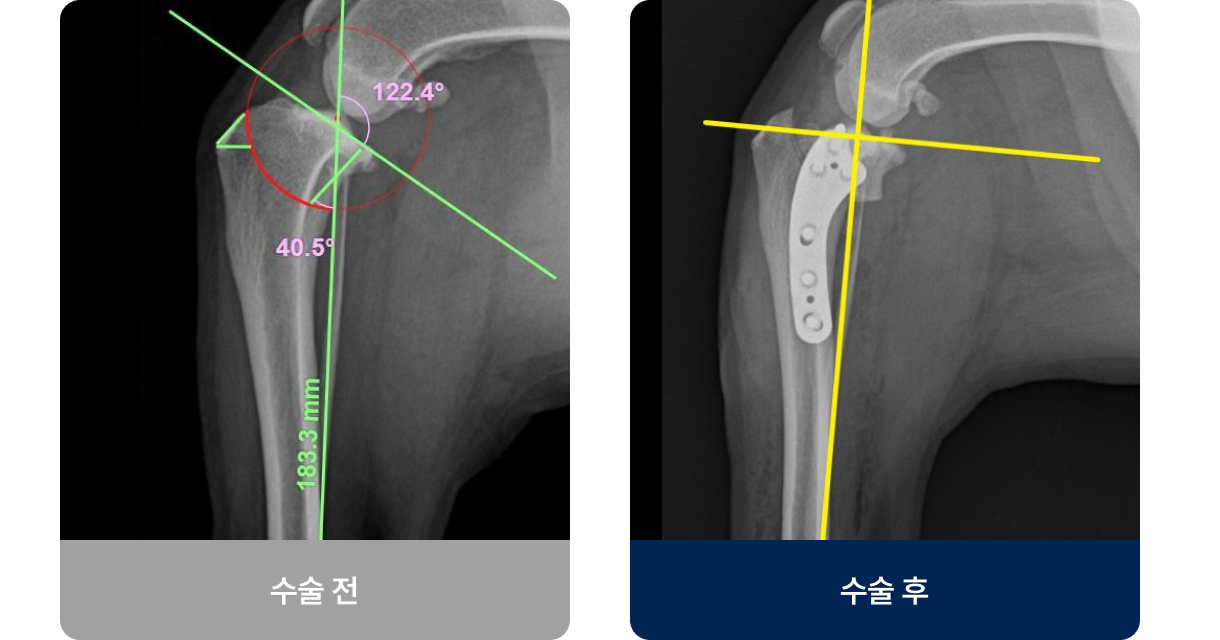

뼈의 연속성이 끊어진 상태로, 충격(낙상·교통사고)이나 병적 요인으로 발생합니다. 갑자기 다리를 절고 신음소리를 내거나 움직이지 않고 일어서거나 걷지 못하는 증상을 보입니다. 대부분 수술이나 깁스 고정을 통해 치료 후, 일정 기간의 휴식과 재활치료를 통해 근력과 관절 운동을 회복해야 합니다.

외과적 치료법(수술적 치료)

수술법은 골절 부위·형태·체중에 따라 달라지지만, 현재 플레이트 고정술이 가장 널리 사용되고 있습니다.